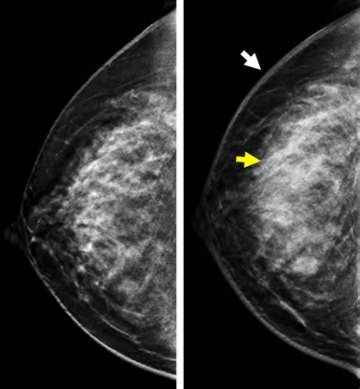

So, why is ultrasound for inflammatory breast cancer such a big deal? Well, traditional mammograms, while excellent for detecting many types of breast cancer, can sometimes miss IBC. This is because IBC often causes diffuse changes throughout the breast, like skin thickening and increased fluid in the breast tissue, rather than a distinct mass. Ultrasound, on the other hand, is fantastic at visualizing these subtle changes. It uses sound waves to create detailed images of the breast’s internal structures. For IBC, an ultrasound can help doctors see:

Think of it this way: a mammogram is like a general overview, while an ultrasound is like a high-resolution zoom lens that can pick up finer details. This makes it an indispensable tool, especially when a patient presents with symptoms suggestive of IBC. Doctors might order an ultrasound even if a mammogram appears normal, simply because the clinical signs are concerning. The ability of ultrasound to differentiate between solid masses, cysts, and areas of inflammation is also a significant advantage. For IBC, the inflammation and blockage of lymphatics are key features that ultrasound can highlight better than other methods. This detailed imaging allows for a more accurate assessment of the extent of the disease and helps in distinguishing IBC from other conditions that might cause similar-looking symptoms, like benign infections. Ultimately, the goal is to get the most accurate diagnosis as quickly as possible, and ultrasound plays a starring role in achieving that for patients suspected of having inflammatory breast cancer.

• Mammography: This is your standard breast screening tool. It uses X-rays to create images. Mammograms are great at detecting calcifications and distinct masses, which are common in other types of breast cancer. However, with IBC, which often lacks a distinct lump and causes diffuse skin thickening and inflammation, a mammogram might appear normal or show subtle changes that aren’t definitive. So, while it’s often done, it might not be the most sensitive tool for IBC itself.

So, while mammograms are crucial for general screening, and MRIs are powerful for detailed staging, ultrasound often takes the lead when it comes to the initial suspicion and detailed assessment of IBC due to its ability to visualize the specific inflammatory changes characteristic of this aggressive cancer. It provides a complementary, and sometimes superior, view for this particular condition. Think of them as a team, each with their own strengths, working together to get you the best possible diagnosis and care. The accessibility and real-time imaging capabilities of ultrasound make it an invaluable tool in the prompt identification of IBC.